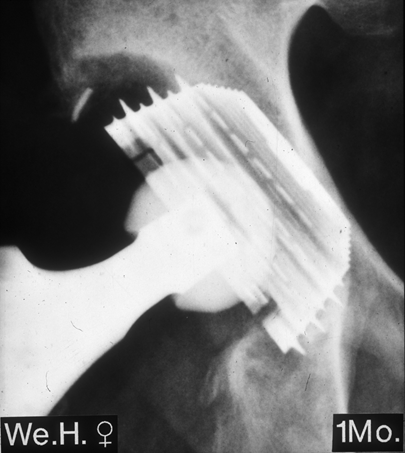

Postoperatives Bild

Monitorgezielte Röntgenaufnahme der Bicon-Pfanne, ein

Monat postoperativ. Im oberen Anteil ist die Pfanne

aufgrund des vorhandenen Defektes nicht mit Knochen

bedeckt.

Zustand nach Austausch beider Komponenten durch

eine Bicon-Pfanne sowie einen SLR-Schaft.

Röntgen 12 Jahre nach der Austauschoperation

sind Schaft und Pfanne stabil eingebaut. Die Patientin ist völlig beschwerdefrei und unbegrenzt gehfähig.

Monitorgezielte Röntgenaufnahme

der Bicon-Pfanne, 12 Jahre postoperativ.

Der Knöcherne Defekt um den oberen

Pfannenbereich hat sich durch neugebildetes

Knochengewebe fast vollständig aufgefüllt.